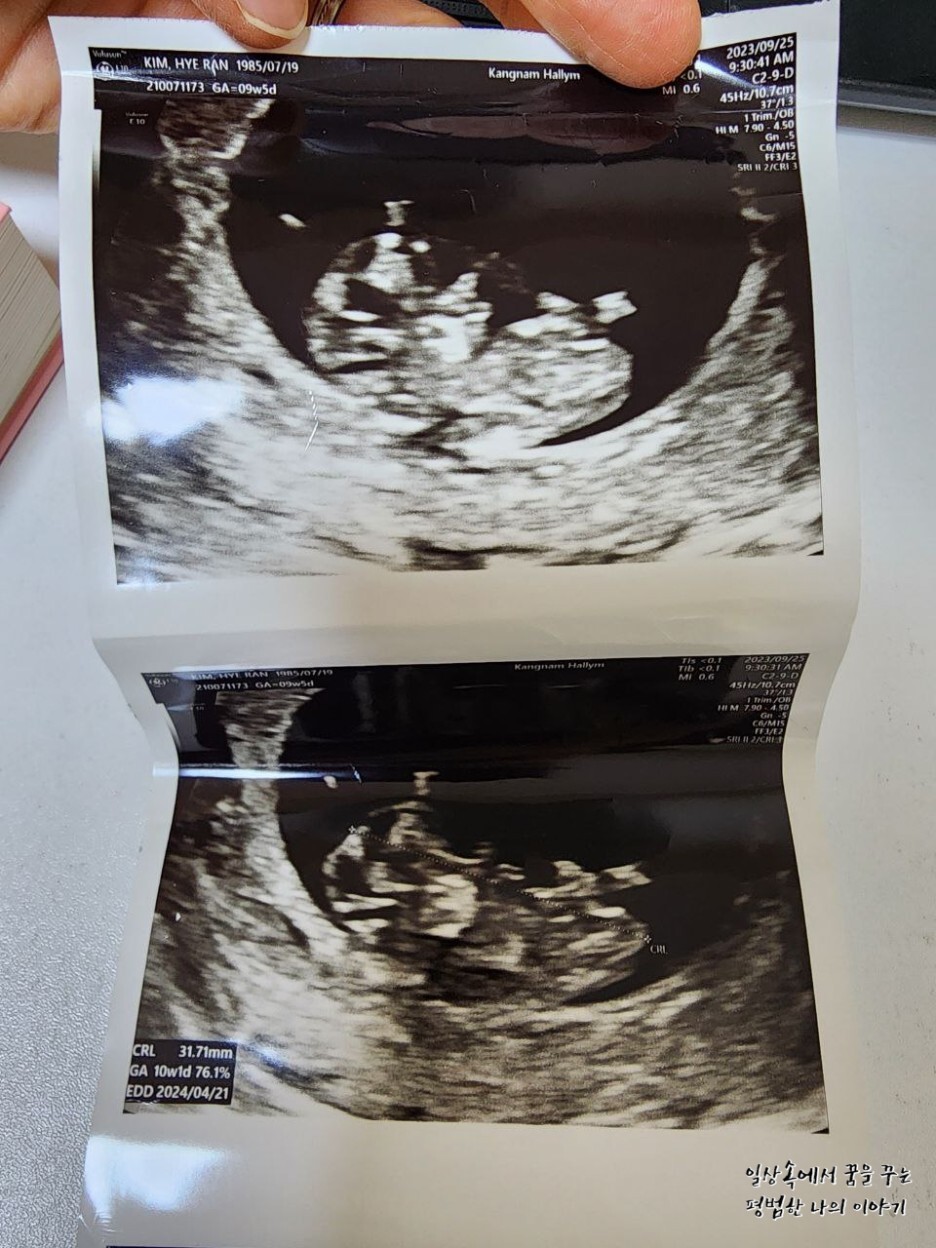

EDD(Expected Date of Delivery, 출산 예정일): 2024년 4월 21일

CRL(Crown-Rump Length, 태아의 머리부터 엉덩이까지의 길이): 31.71mm

2주 만에 만난 레오나는 여전히 내 눈에 귀여운 젤리 곰 형태를 하고 있었다. 2주 사이에 16.72mm에서 31.71mm로 두 배나 길어져 있었다. 31.71mm라고 해봐야 정말 콩알만 한 크기이지만 그 작은 크기에도 얼굴, 손 그리고 발까지 초음파로 확인이 가능하다. 출산 예정일은 지난번에 비해 3일 앞당겨졌는데 아기의 크기에 따라 계속 바뀔 수 있으므로 대략 4월 셋째 주쯤 출산하겠구나 예상하고 계획을 짜기 시작했다.